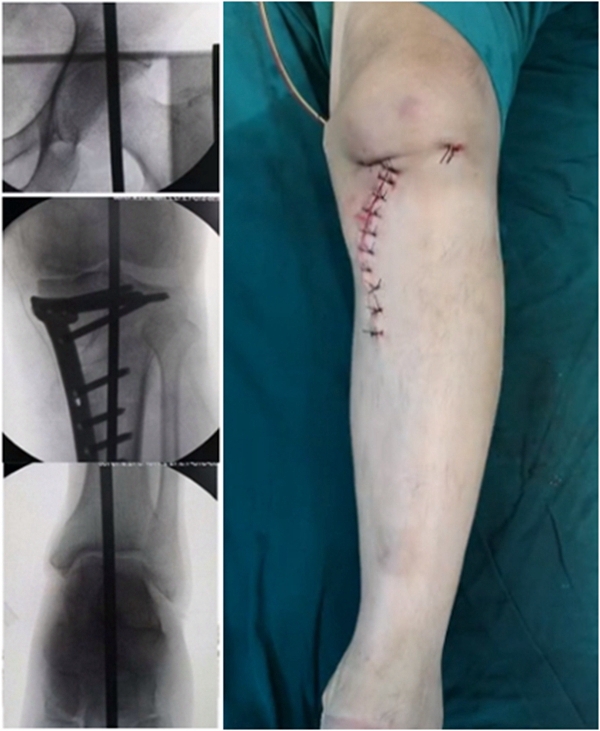

典型病例,女性,56岁,农民右膝内翻18度。

术前影像

术中影像

结合影像学来看,该患者单纯用闭合截骨或开放截骨,对肢体均有影响,所以决定采用混合型截骨。术中混合截骨旋转中心选在内外1/3处,先做闭合楔,然后顺势将开放楔敲开,达到术前设计的目标力线。术后随访力线达到要求。

术后X线